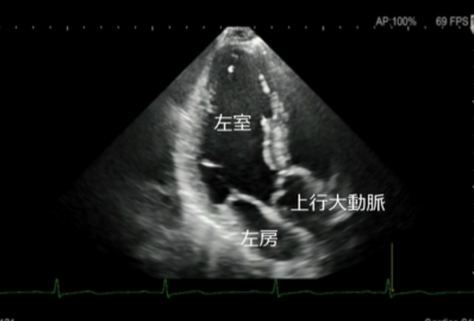

心エコー検査は、超音波を用いて心臓の形や動き、血流の流れを詳しく観察する検査です。

放射線を使用しないため、身体への負担が少なく、安全に繰り返し行うことができます。

エコー(心臓超音波)検査

- このようなことが分かります

弁膜症の評価

心臓の弁(大動脈弁・僧帽弁など)の開き具合や逆流の有無を確認します。

弁の狭窄や逆流の程度を評価し、治療方針の判断に役立てます。 - 心筋の働き(ポンプ機能)の評価

心臓がどのくらいしっかり血液を送り出せているか(収縮機能)を確認します。

心筋梗塞後の機能低下や、拡張型心筋症などの診断にも重要です。 - 心不全の原因検索

息切れやむくみなどの心不全が疑われる場合、その原因が弁膜症によるものか、心筋の

弱りによるものかを詳しく調べます。 - その他

心肥大の有無・心臓内血栓の確認・先天性心疾患の評価・肺高血圧症の推定 など - 検査について

検査時間はおおよそ20~30分程度です。

ベットに横になっていただき、胸にゼリーを塗ってプローブ(探触子)を当て観察します。痛みはありません。

当院では、循環器疾患の早期発見と適切な治療につなげるため、症状がある方は、もちろん、健診等で指摘された方にも心エコー検査を行っております。

お気軽にご相談ください。